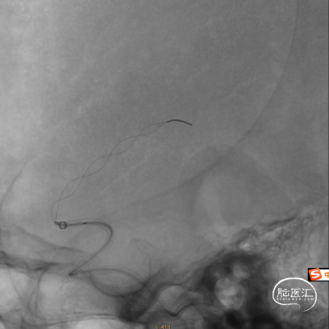

输送微导丝微导管小心通过闭塞段,微量造影,远端血管显影,回撤微导丝后推送并释放4x30mm Syphonet®取栓支架,可见Syphonet®取栓支架清晰显影,支架打开良好。